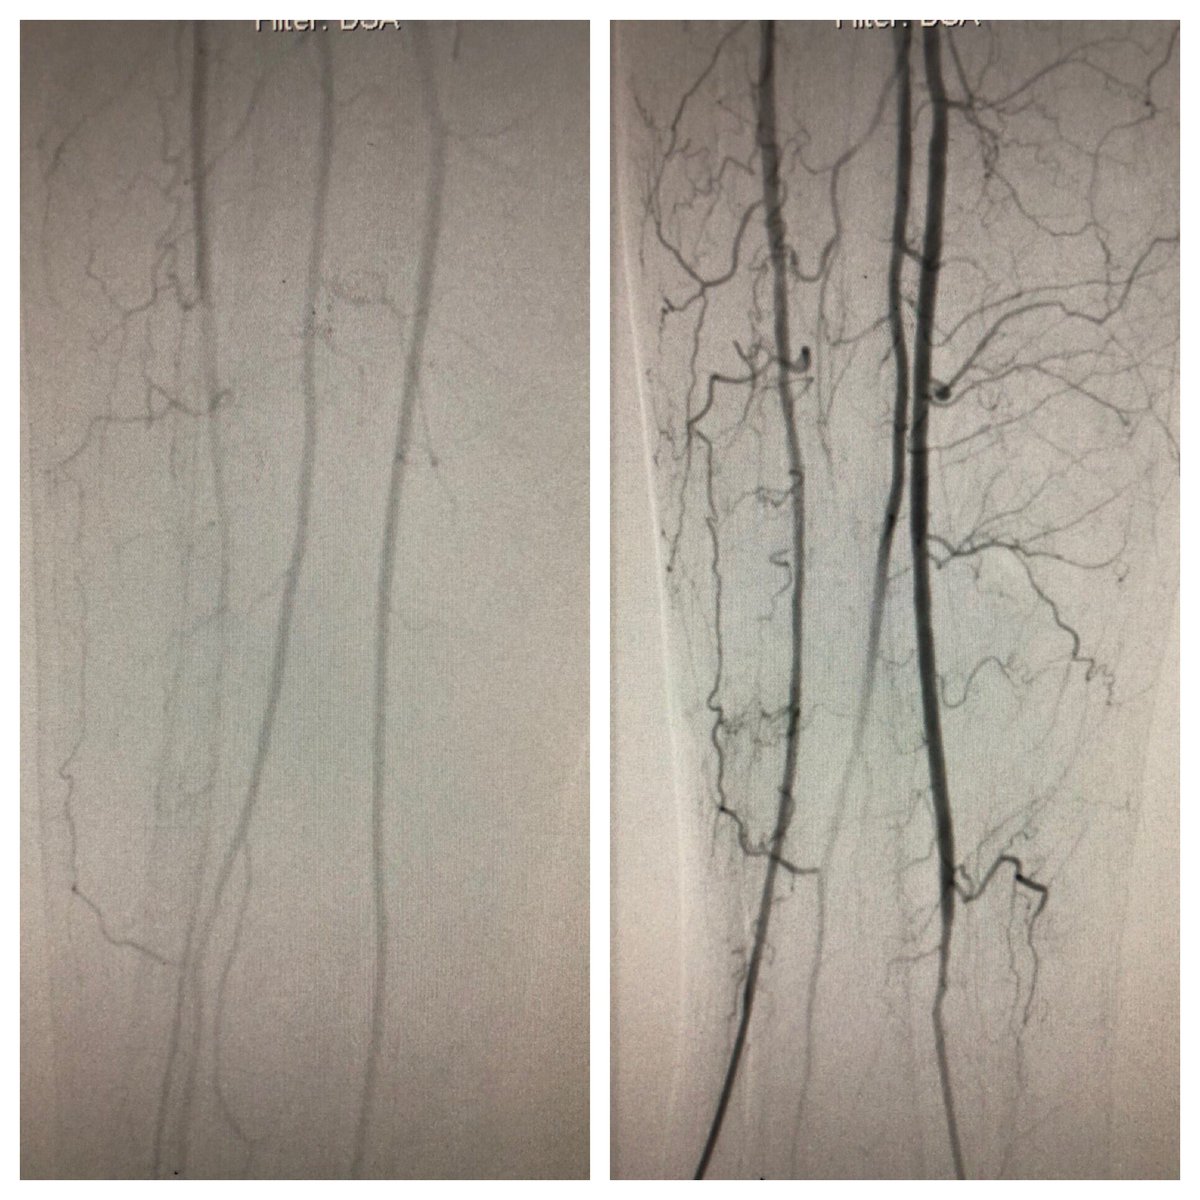

Late case before time off for the 4th! Open toe wound w/ osteo. Antegrade crossing of occluded peroneal. Tibial access to cross long segment ATA occlusion after failed antegrade attempt. Initial access too close to distal cap so moved distal #CLI #SCAIPAD #wifeissounderstanding